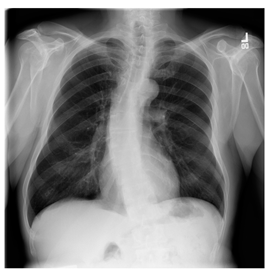

NIH Database

ANIH is an X-ray type image database collecting chest medical images. Some samples are shown in Figure 12c.

Figure 12. Sampled images in the tested benchmark databases: (a) Breast-MRI-NACT-Pilot (breast), (b) ACRIN-DSC-MR-Brain (brain), (c) NIH (chest), (d) Lung-PET-CT-Dx (lung), (e) Prostate-MRI (prostate), and (f) Other grayscale standard images.